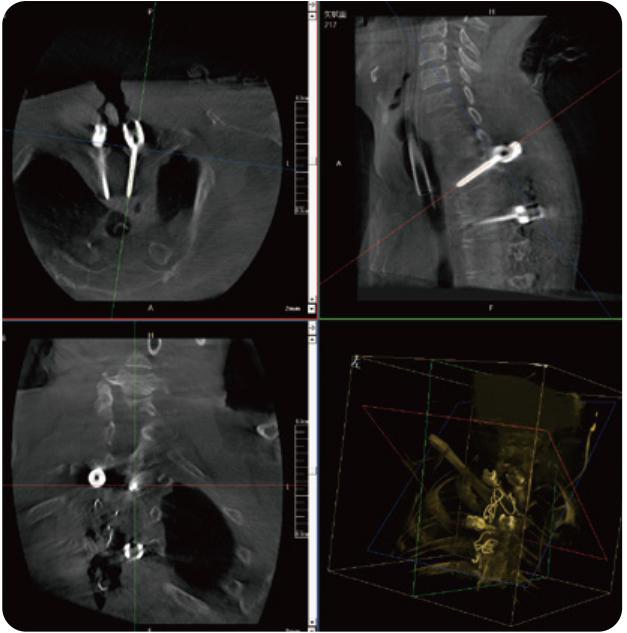

PL300B可應(yīng)用于多節(jié)段脊柱外科手術(shù),輔助醫(yī)生定位病灶部位,為脊柱外科手術(shù)(經(jīng)皮椎體成形術(shù)、椎弓根螺釘內(nèi)固定術(shù)等術(shù)式)提供術(shù)前手術(shù)流程規(guī)劃、入釘位置、角度可視化引導(dǎo),模擬仿真入釘輔助。

PL300B搭配普愛醫(yī)療自主研發(fā)生產(chǎn)的平板3D C形臂,借助一體化自適應(yīng)配準(zhǔn)( 軌跡配準(zhǔn))技術(shù),通過追蹤C(jī)形臂三維采集軌跡,自動完成圖像坐標(biāo)建立和系統(tǒng)坐標(biāo)配準(zhǔn)。配準(zhǔn)精度更高,操作步驟少,系統(tǒng)運(yùn)作效率高。